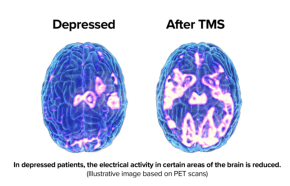

TMS works on circuits in the brain, neurons/nerve cells that fire together and wire together to form discrete but correctable networks. The Central Executive Network CEN is underperforming leading to poor concentration and forgetfulness in depression. The Default Mode Network DMN in depression is overactive, leading to brooding, ruminating negative thoughts. The Salience Network SN is your brain’s channel selector and instead of tuning in your creative, supportive, optimistic Central Executive Network, it’s tuned into the morbid Default Mode Network. By stimulating and strengthening the connections of the CEN and SN and turning down the DMN, health is restored and the depression remits. This is accomplished by high frequency 10 Hz repetitive magnetic stimulation from an MRI-strength 2 tesla stimulator and fluid-filled figure-of-8 coil. The induces a current in the brain much like a wireless charger for your cell phone or electric toothbrush placed on top of it. It’s a non-invasive means of stimulating the brain with little-to-no side effects, no memory loss and most treatments take only 23 minutes. TMS of Knoxville is proud to be the first TMS clinic in east Tennessee and the first in the eastern US to purchase and use the first cooled, fluid-filled coil made by MagVenture. They are a Danish company with a long history, making the first liquid-cooled coil and many other innovations.

TMS works on circuits in the brain, neurons/nerve cells that fire together and wire together to form discrete but correctable networks. The Central Executive Network CEN is underperforming leading to poor concentration, forgetfulness in depression. The Default Mode Network DMNin depression is overactive, leading to brooding, ruminating negative thoughts. The Salience Network SN is your brain’s channel selector and instead of tuning in your creative, supportive, optimistic Central Executive Network, it’s tuned into the morbid Default Mode Network. By stimulating and strengthening the connections of the CEN and SN and turning down the DMN, health is restored and the depression remits. For more info click below: